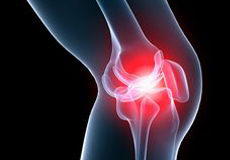

Knee Arthritis

The joint surface is covered by a smooth articular surface that allows pain-free movement in the joint. Arthritis is a general term covering numerous conditions where the joint surface or cartilage wears out. This surface can wear out for several reasons; often the definite cause is not known. Arthritis often affects the knee joint. When the articular cartilage wears out, the bone ends rub on one another and cause pain.

Knee Osteoarthritis

Osteoarthritis also called degenerative joint disease, is the most common form of arthritis. It occurs most often in older people. This disease affects the tissue covering the ends of bones in a joint (cartilage).In a person with osteoarthritis, the cartilage becomes damaged and worn out causing pain, swelling, stiffness and restricted movement in the affected joint.

Knee Pain

Knee pain is a common condition affecting individuals of different age groups. It not only affects movement but also impacts your quality of life. An injury or disease of the knee joint or any structure surrounding the knee can result in knee pain. A precise diagnosis of the underlying cause is important to develop an appropriate treatment plan.